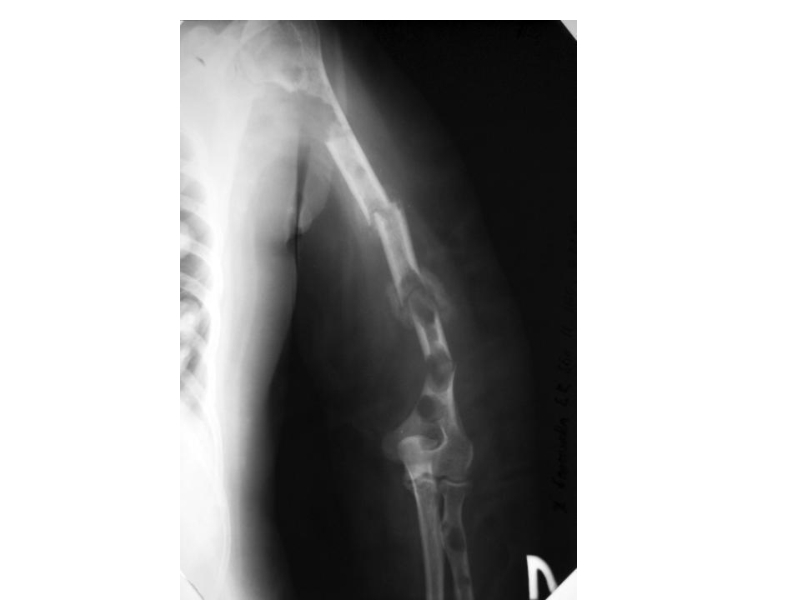

Слайд 25Клинические проявления ММ

Поражение костей

Множественные остеолитические очаги повреждения плоских костей

и эпифизов трубчатых костей

Диффузный остеопороз (остеопения)

Костные переломы

Уменьшение роста (вертебральный коллапс)

Болевой

синдром